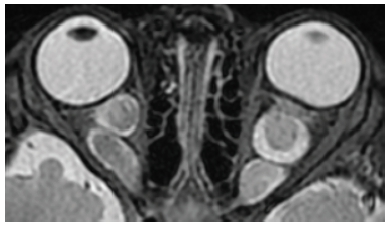

Diagnosticul acestei tumori se face prin examinare oftalmologică. Stadializarea și planul de tratament se fac în urma completării cu examinarea oftalmologică în anestezie generală, completată de examen RMN. Tratamentul este multidisciplinar, general prin chimioterapie, local prin chimioterapie, radioterapie, laserterapie/chirurgical. Succesul tratamentului depinde de stadiul diagnosticului.

Retinoblastom